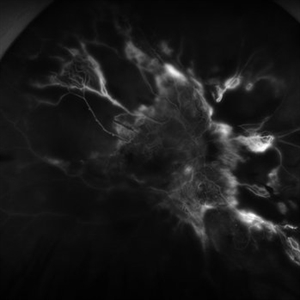

Severe Proliferative Diabetic Retinopathy

Jan 10 2024 by Ahmad B. Tarabishy, MD

33 year old female with 1 month history of vision loss right eye. Severe PDR was noted with VH and a TRD with severe FVP present OD.

Photographer: Sharon Story, Lakeland Eye Clinic

Imaging device: Optos

Condition/keywords: diabetic blindness, fibrovascular proliferation, nonperfusion diabetic retinopathy, peripheral retinal nonperfusion, proliferative diabetic retinopathy (PDR), tractional retinal detachment